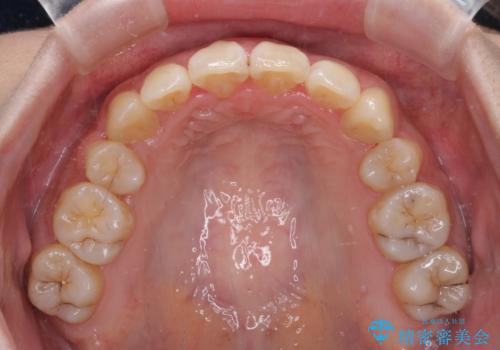

- 八重歯と叢生を気にして来院された患者様です。

上下の前歯が非接触であり、叢生や八重歯が顕著であったため、上顎左右第一小臼歯2本を抜歯して排列することとしました。

抜歯により移動量が多くなるため、ワイヤーや補助装置を活用し、その後インビザラインによる矯正治療を行うこととしました。